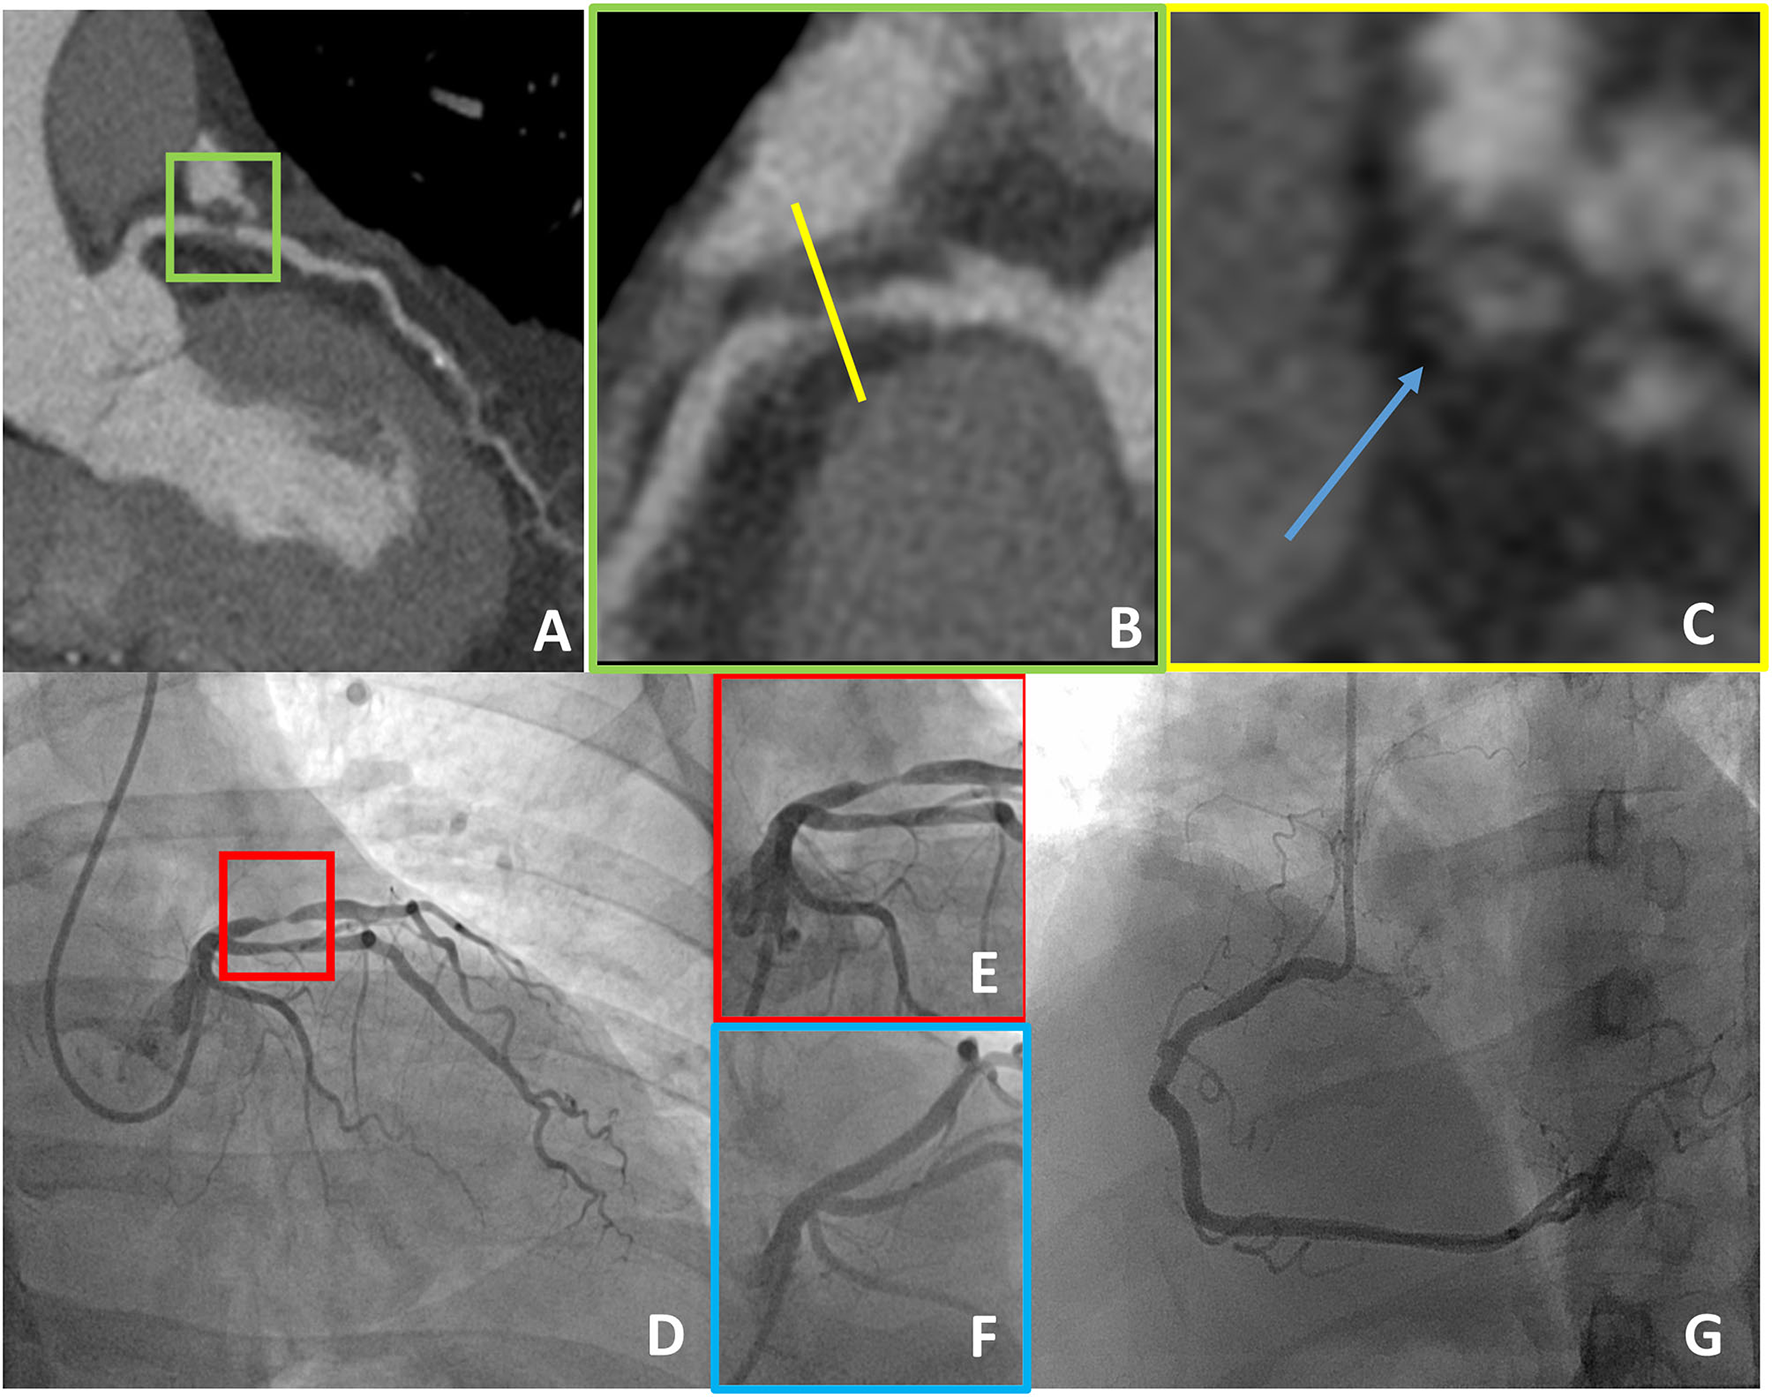

Coronary CT angiography showed no CAD in 14 patients (24.1%), non-obstructive CAD in 30 (51.7%) patients, and obstructive CAD in 14 (24.1%) patients. None of the patients with normal coronary arteries at CCTA was sent to the catheterization laboratory for non-deferrable ICA (Table 1). A total of 10 patients were sent to ICA based on the CCTA results and in all but one severe CAD was confirmed and treated accordingly. CCTA showed critical/subocclusive (>90% diameter stenosis) lesions in six patients. All underwent percutaneous revascularization after ICA confirming the CCTA findings (Figure 2). The only patient who was not revascularized had a calcified non-high risk plaque of the proximal left anterior descending artery (LAD) and was referred to ICA due to typical angina with suspected left main CAD (Table 2).

Figure 2

A case example of a 55-year-old man with the typical chest pain in whom CCTA detected critical stenosis of the proximal LAD (A,B), showing at the same time high-risk plaque features (positive remodeling and low-attenuation plaque as demonstrated in a short axis view, blue arrow in C). The patient underwent ICA that confirmed subocclusive disease of the proximal LAD that was treated with PCI (D–G). CCTA, coronary computed tomography angiography; LAD, left anterior descending artery; ICA, invasive coronary angiography; PCI, percutaneous coronary intervention.